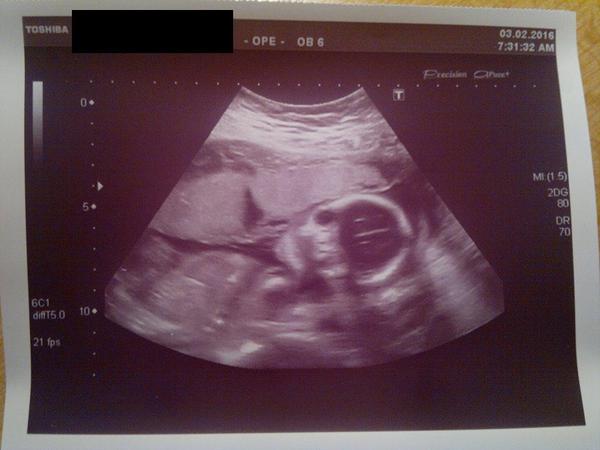

Je to holčička nebo chlapeček? Foto ultrazvuku

@estrellita tak podruhe potvrzena pipinka

Doktor si prave take nebyl jisty.Ale priklanel se 60% ke klukovi 🙂

@luccyj toto jsme videli na ultrazvuku na genetice ve 20 tydnu a pani doktorka rekla ze je to klucik. a intuice me zklamala celou dobu jsem byla presvedcena ze je to holcicka 🙂